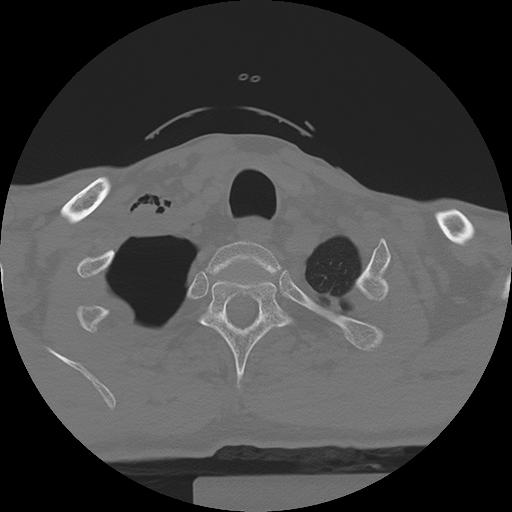

11 HUESO,,Axial,2.0,HUESO,,